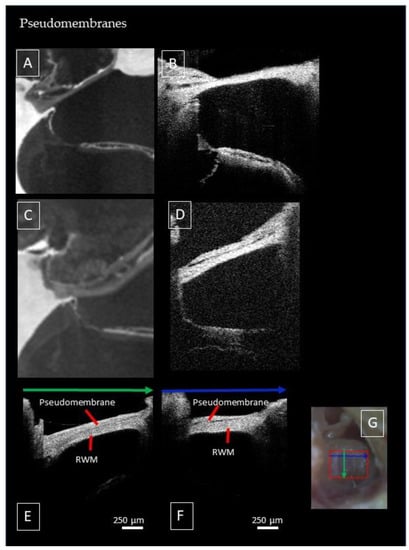

3.5. Factors Limiting Imaging through the RWM